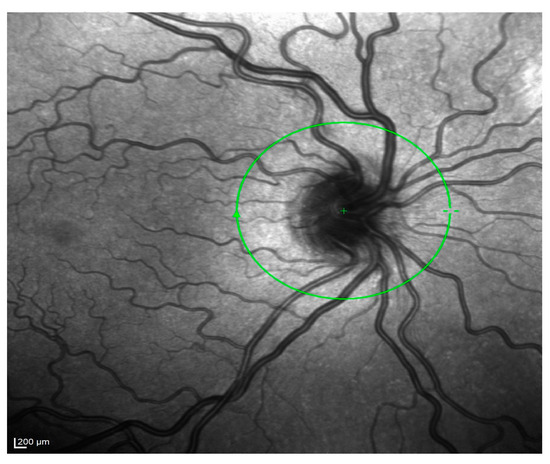

- Hernández-Quintela, E.; Mayer, F.; Dighiero, P.; Briat, B.; Savoldelli, M.; Legeais, J.-M.; Renard, G. Confocal microscopy of cystic disorders of the corneal epithelium. Ophthalmology 1998, 105, 631–636. [Google Scholar] [CrossRef]

- El Sanharawi, M.; Sandali, O.; Basli, E.; Bouheraoua, N.; Ameline, B.; Goemaere, I.; Georgeon, C.; Hamiche, T.; Borderie, V.; Laroche, L. Fourier-domain optical coherence tomography imaging in corneal epithelial basement membrane dystrophy: A structural analysis. Am. J. Ophthalmol. 2015, 159, 755–763. [Google Scholar] [CrossRef]

- Rosenberg, M.E.; Tervo, T.M.; Petroll, W.M.; Vesaluoma, M.H. In vivo confocal microscopy of patients with corneal recurrent erosion syndrome or epithelial basement membrane dystrophy. Ophthalmology 2000, 107, 565–573. [Google Scholar] [CrossRef] [PubMed]

- Kobayashi, A.; Yokogawa, H.; Sugiyama, K. In vivo laser confocal microscopy findings in patients with map-dot-fingerprint (epithelial basement membrane) dystrophy. Clin. Ophthalmol. 2012, 6, 1187–1190. [Google Scholar] [CrossRef] [PubMed][Green Version]